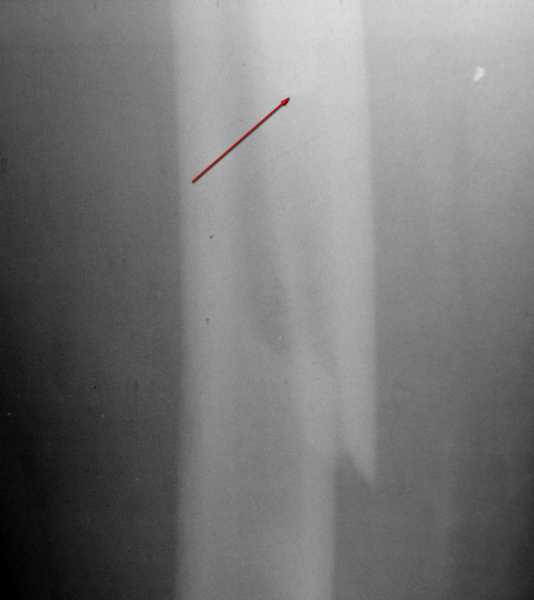

Вот фрагменты этих снимков с более различимыми областями интереса.

Видимо, тут надо добиваться точной репозиции этой спирали вдоль протеза, чтобы воссоздать ложе для ножки.

1. Спасибо за детализацию. Всё увидел.

2. Каким образом по снимку Вы можете определить, насколько стабильно стоит в данном случае бедренный компонент? Мы даже не видим, какая по размеру площадь поверхности кости контактирует с цементом. Это как раз не просто можно, но и нужно определить именно интраоперационно. Не исключён вариант, что во время операции оставшийся цемент может "отойти" вместе с ножкой (имхо, опыт показывает, что цемент крепче фиксируется к компоненту эндопротеза, нежели к костному ложу) и тогда после репозиции и фиксации фрагментов серкляжами надо будет думать о press-fit или ревизионной ножке. Тут ведь ещё вот какой момент: даже анатомически идеально точно произведённая репозиция фрагментов мало что даст в смысле увеличения стабильности - будет отсутствовать цементная фиксация ножки к стенкам костно-мозгового канала на том участке, где цемент уже отошёл при травме. Поэтому давать прогнозы и планировать что-то совершенно конкретное, основываясь исключительно на снимках - побоялся бы.